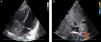

Caso clínicoNiña de 10 años que refería cuadro de 8 días de evolución de fiebre de hasta 38,7°C, mialgias y astenia. A la exploración, la paciente estaba estable, con buen estado general, febricular, con discreta palidez cutánea y se auscultaba un soplo sistólico ii/vi que no se modificaba con los cambios posturales. En la analítica destacaba una anemia microcítica e hipocroma (Hb 8,9g/dl, VCM 77 fl, HCM 23,2pg), VSG elevada (84mm/h) y un fibrinógeno elevado (7,6g/L). Se realizó una radiografía de tórax que no mostraba alteraciones y un ecocardiograma en el que se objetivó una tumoración auricular derecha de 45×31mm de diámetro, móvil, adherida al tabique interauricular y con una ecogenicidad similar a la del miocardio (fig. 1). No causaba obstrucción del flujo pero sí insuficiencia tricuspídea leve-moderada (gradiente VD-AD de 18mmHg) y cierta dificultad de llenado auricular por obstrucción de la vena cava inferior. Con el diagnóstico de tumor auricular derecho, se realizó exéresis de la masa y de la base de implantación bajo circulación extracorpórea, con plastia posterior del septo mediante parche pericárdico. No hubo incidencias. En el postoperatorio inmediato se mantuvo hemodinámicamente estable, con discreto edema agudo de pulmón que mejoró con tratamiento diurético. Inició dieta enteral a las 24-48 h, siendo bien tolerada, y no presentó signos clínico-analíticos de infección. A nivel hematológico, presentó recuperación progresiva de la anemia. Durante el ingreso se estudiaron la función tiroidea y los niveles de cortisol, y se examinó la piel, descartándose la presencia de nevus que hicieran pensar en el síndrome de Carney. La anatomía patológica de la pieza tumoral finalmente confirmaba el diagnóstico de mixoma auricular (figs. 2 y 3).